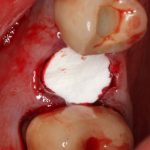

Изоляция области аутографта и имплантатов барьерной мембраной.

Перекрывать костный блок барьерной мембраной или оставить так? По этому вопросу есть много мнений. Между тем, в публикации по методике есть ясное показание, когда это требуется.

Конкретно в этом клиническом случае между костным аутотрансплантатом, ложем и имплантатами есть пустое пространство. Если его не изолировать от мягких тканей, они прорастут и осложнят интеграцию аутографта. Поэтому я решил перекрыть костный блок барьерной мембраной, пусть это делает хирургическую операцию немного дороже.

— я использовал барьерную мембрану Geistlich Bio-Gide, которая имеет две разные поверхности: с одной стороны она рыхлая «адгезивная», с другой — гладкая и прочная. Как укладывать — на результат не влияет, но в плане удобства рыхлую поверхность мы «приклеиваем» к тому, на чем требуется барьерную мембрану удержать. В данном случае хотелось бы удержать её на костной поверхности — следовательно, мы укладываем её рыхлой поверхностью к кости.

— много лет мы используем антибиотики для интраоперационной профилактики инфекционно-воспалительных осложнений. Уже в то время мы пришли к выводу, что удобнее всего — порошки антибактериальных препаратов для приготовления раствором: дешевые, стерильные, в удобной упаковке. Прямо в виде порошка их можно добавлять в графт, растворы для ирригации, либо использовать так, как показано на фото. Еще мы используем порошок антибиотика для изготовления пасты, которой обрабатываем имплантаты в процессе ревизии или при лечении периимплантита. Это удобнее и эффективнее, чем интраоперационное использование жидких форм антибактериальных препаратов.

— ты знаешь, что барьерная мембрана может выполнять две функции, каркасную и изолирующую. Первая функция требует обязательной фиксации и натяжения, вторая — нет. В нашем случае «каркасом» регенерата является костный блок, а барьерная мембрана нужна только для изоляции. Поэтому она не требует натяжения и фиксации пинами.

После я внимательно проверил, что костный блок и имплантаты полностью перекрыты. Теперь рану можно ушивать.